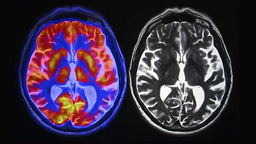

Research Poster: Evaluating Current Methods For Enhancing CT Imaging Using Contrast Agents

The long-term aim of my project is to optimise existing CT technology to deliver improved patient outcomes. Having an accurate up to date review of the current contrast agents employed by clinicians and research groups can aid in their development and eventual release in hospitals. This becomes especially important when considering remote or poorer areas, where a portable CT scanner paired with an efficient contrast agent would have the power to provide an earlier diagnoses and enhanced scans for surgery or treatment. To disseminate my research I aim to have a published research review paper by the end of year two of the Laidlaw programme.